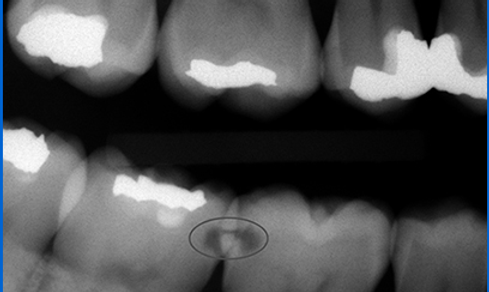

Počínající kaz

Pomocí intraorálního rentgenu byl lékařem zjištěn počínající kaz, který nebolí. Necháme-li kaz růst až do fáze, kdy začne zub bolet, bude nutno přeléčit kořenový systém zubu - endodoncie.